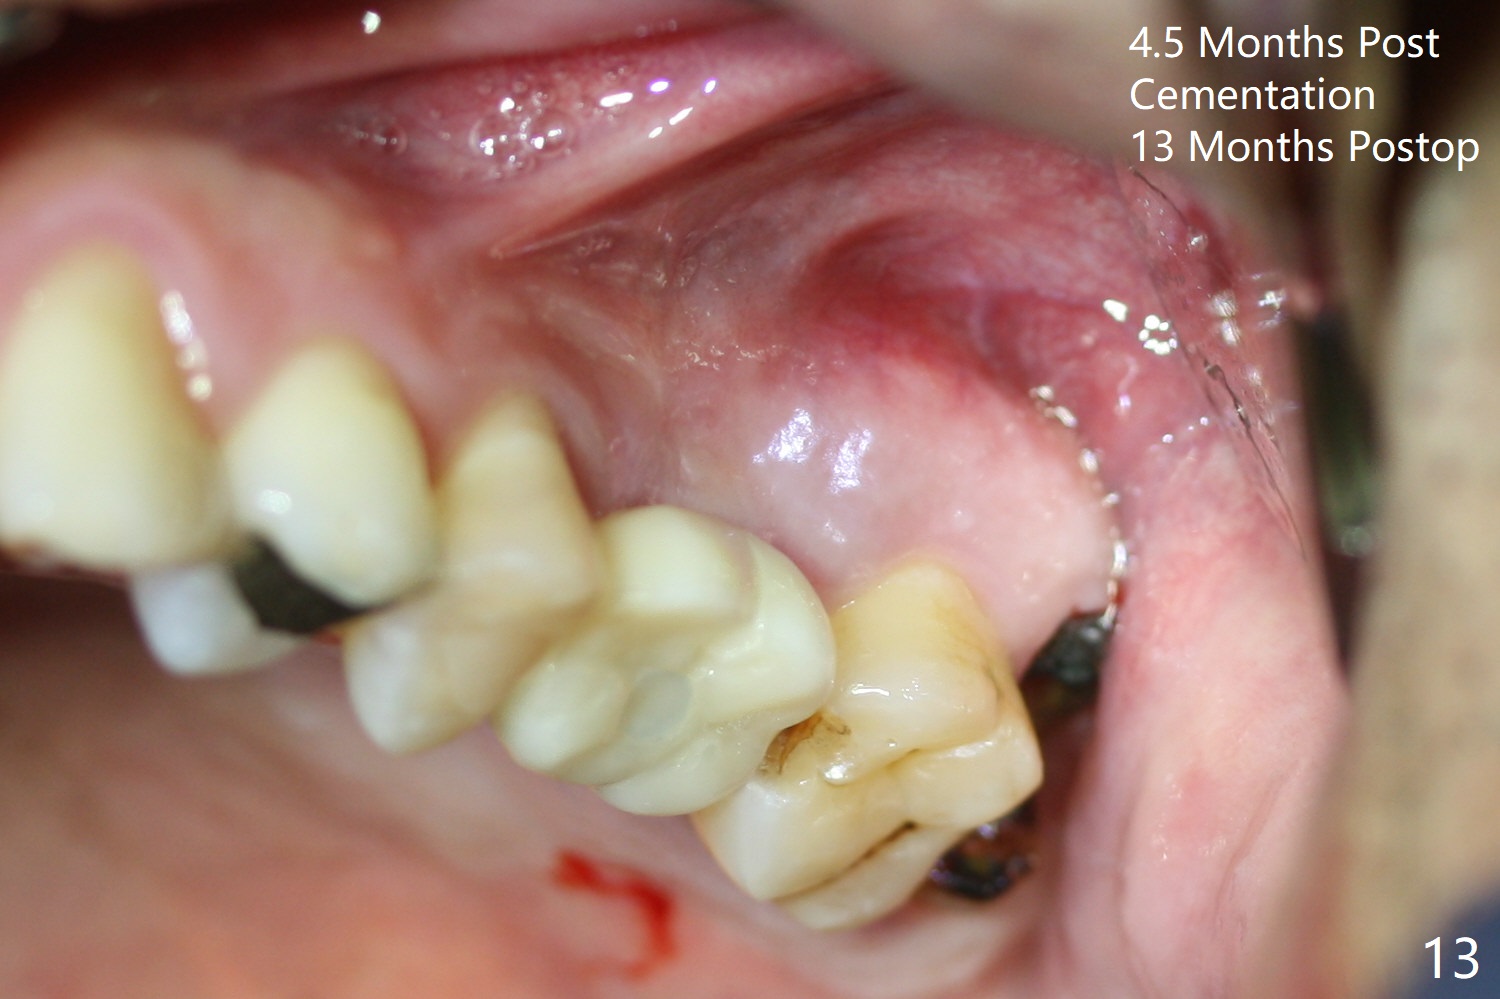

After extraction of the distobuccal residual root of the tooth #14 (Fig.1 arrow), the gingiva around the socket does not look like the keratinized one (Fig.2 *). An osteotomy through the distobuccal socket would seem too buccal for immediate implant. The palatal gingiva feels too tough to be stretched. An incision is made (Fig.3 dashed line); with elevation, the thick flap is transferred buccally (curved arrow). An osteotomy is initiated in the palatal bone with 1.5 mm drill, followed by Magic Expanders until 4.3 mm for 11 mm (Fig.4,5). Following Magic Drill 3.8x13 mm, the sinus membrane is found to be perforated. The latter is repaired with Osteogen plug. A 4.5x9 mm IBS implant is placed with 50 Ncm (Fig.6). Osteogen plug and allograft (Fig.7 *) are inserted into the remaining distobuccal socket (reduced after bone expansion). When a 5.5x4(4) mm abutment is placed, the transferred flap appears to be adapted to the distobuccal defect (Fig.8 *). Later one suture is placed for fixation. After provisional insertion, periodontal dressing is applied. Nine days postop, the periodontal dressing dislodges. When the loose provisional is removed for recementation, the flap seem to have healed (Fig.9 *). The gingiva heals around the abutment 5 months postop (Fig.9); the distal socket appears to heal while the bone graft remains at the crest (Fig.11,12). When #30 develops buccal abscess, the patient masticates on the left, leading to loss of composite at #13 (Fig.14); in fact the abutment at #14 is incompletely seated.